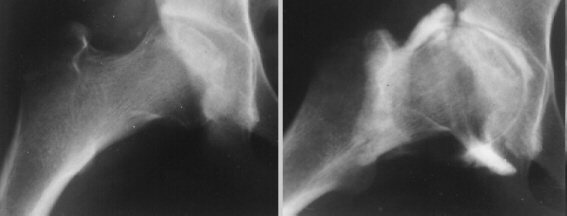

This 12 year old girl sustained a right femoral neck fracture by falling from a balcony(image 1). After 2 weeks of bed-rest, she was started walking with crutches. She completely returned to normal activities 6 months after the trauma. She was beginning to complain of the right hip pain 2 years after the trauma(image 2 & 3).

The large posterior surface of the femoral head remained intact therefore a base of the femoral neck osteotomy could be performed to rotate the femoral head forward and into valgus.

The Sugioka osteotomy is an easy procedure and would be the ideal to get the needed intact surface of the femoral head into the acetabulum.